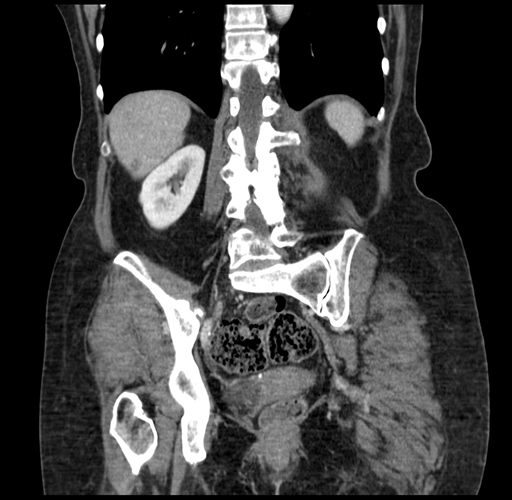

Pre-Chemo: Coronal Venous

Coronal Venous